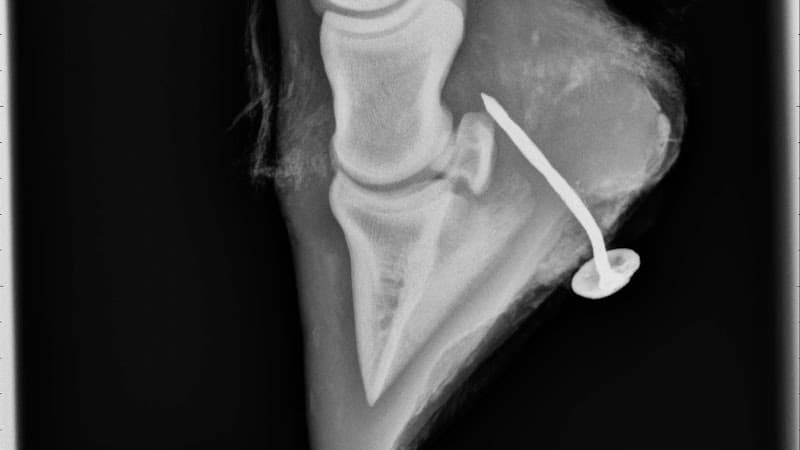

Equine veterinary services are delivered at the horse's usual location using mobile diagnostic equipment. The practice carries digital radiography, ultrasound and endoscopy equipment to enable on-site diagnostic investigations. Routine services include vaccinations, dental care, lameness examinations and pre-purchase veterinary examinations. Emergency call-outs are available for acute conditions including colic, lacerations, eye injuries and foaling difficulties.

Practice Facilities The practice operates a mobile veterinary service with fully equipped vehicles carrying diagnostic and treatment equipment. Digital radiography allows immediate review of x-ray images at the yard. Ultrasound equipment enables assessment of soft tissue injuries, tendons and internal organs. Endoscopy equipment allows examination of the upper respiratory tract and gastric system.